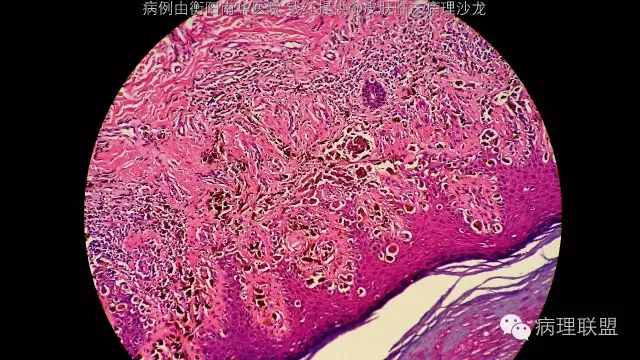

诊断依据,1,临床特点,常发生于老年人,足底,皮疹大于6mm,边缘不规则,色沉不均。2,鳞状上皮上皮脚延长,异型色素细胞沿上皮脚两侧基底层呈连续性增生。3,真皮乳头见灶性异型色素细胞浸润。

这张最明显,异型色素细胞沿上皮脚两侧,基底层呈连续增生

这张图尤其左下方显示真皮乳头层及真皮浅层有灶性异型色素细胞浸润